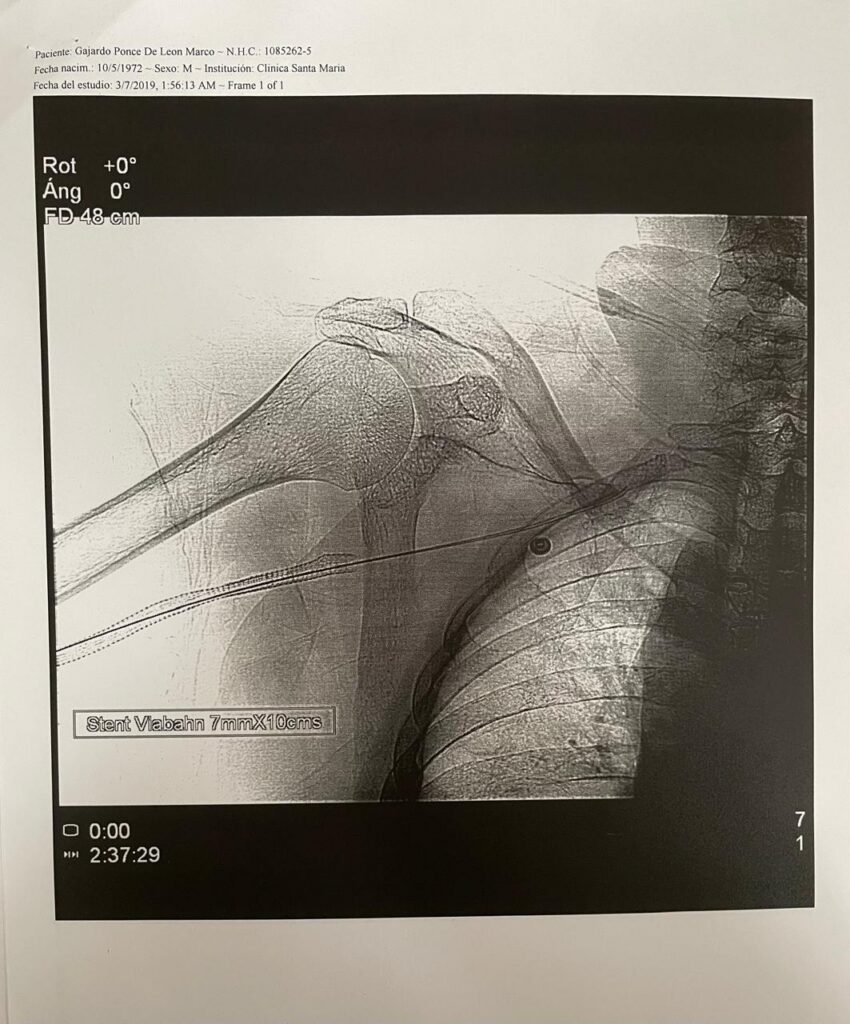

| 2 Stents (2019) |

Stents